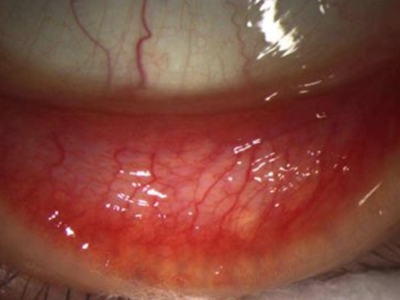

儿童过敏性结膜炎是由于结膜对过敏原产生超敏反应所引起的炎症,是最常见的过敏性眼病,常表现为眼部瘙痒感明显,以及结膜充血等。具体分为季节性过敏性结膜炎、常年性过敏性结膜炎、巨乳头型结膜炎、春季角结膜炎、特应性结膜炎,其中季节性过敏性结膜炎最为常见。

儿童过敏性结膜炎最常见的症状是眼部瘙痒感明显,其他症状包括畏光、流泪、烧灼感等,最常见的体征是结膜充血,充血程度和病情程度有关。其他体征包括眼睑、球结膜水肿,睑结膜细小的乳头增生、滤泡形成。